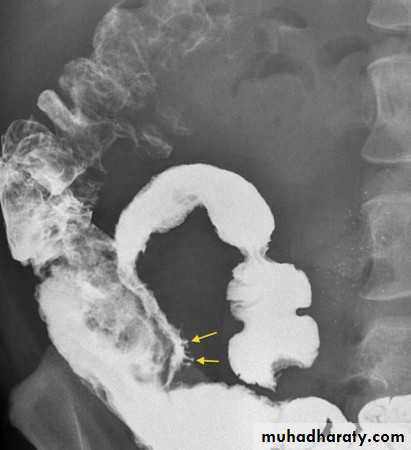

Radiological signs:

• Widespread shallow ulcer is the cardinal sign. Ulcers may be deep in severe cases• Widening of the presacral space in early stage of disease due to peri-rectal edema

• Loss of the normal colonic haustra in the affected portions of the colon

• Narrowing and shorting of the colon giving the appearance of rigid tube (lead-pipe appearance).

• Pseudopolyps ( swollen mucosa between ulcers) seen as filling defects

• Strictures are rare and likely to be due to carcinoma in longstanding disease

• Abnormal dilated ileum due to reflux through an incompetent ileocecal valve